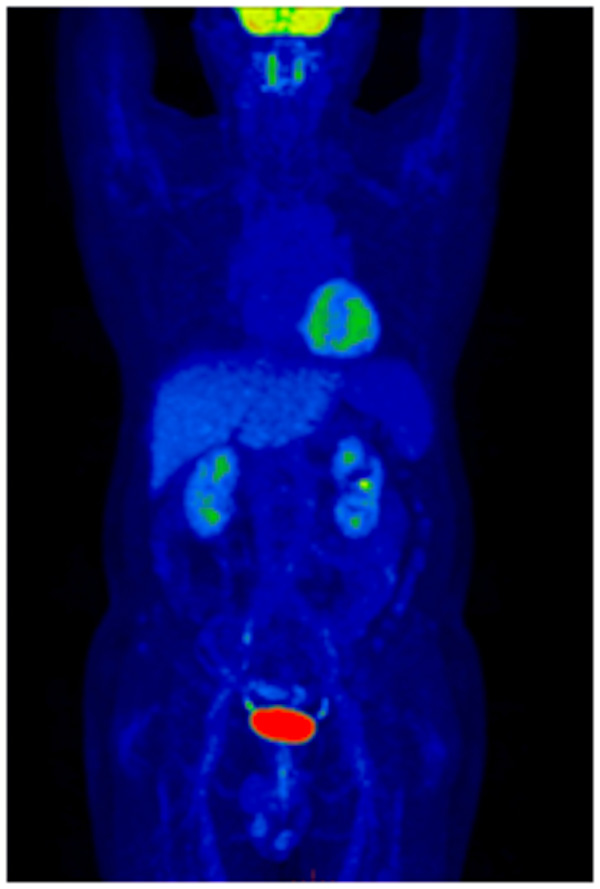

▲患者全身MIP圖:全身多發(fā)淋巴結(jié)淋巴瘤浸潤(rùn)(A)

PET-CT能夠一次獲得全身檢查圖像,除了頸部及腋窩,其他部位的病灶也能一覽無(wú)余,患者的臨床分期發(fā)生了改變,為臨床醫(yī)生選擇治療方案提供了極大的幫助。